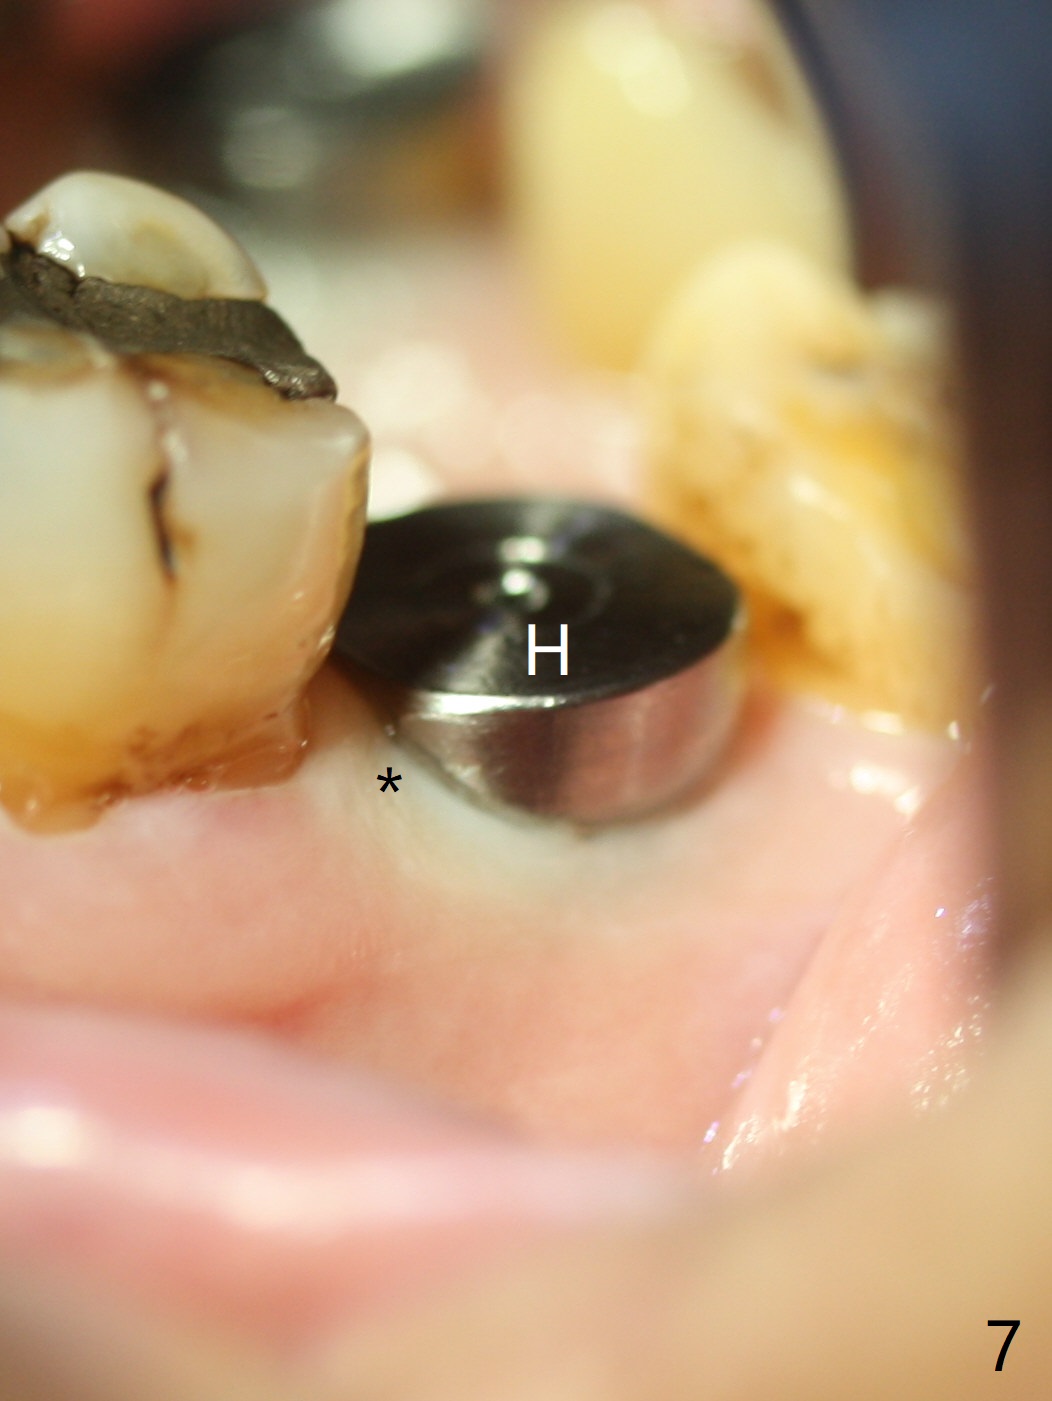

When the mobile tooth #18 with apical granulation tissue is extracted, the socket is large and long (close to the Inferior Alveolar Canal (Fig.2,3 red dashed line). Without drilling, a 7 mm bone level tap does not obtain stability. A 8x17 mm tapered tap reaches the bottom of the socket with minimal stability, but coronally it is close to the tooth #32 (Fig.1). When a 7x14 mm cylindrical tap is placed, it is shy of the bottom of the socket (Fig.2 *), but the trajectory improves. A 7x14 mm tissue-level implant is placed with ~45 Ncm (still not secure) with Vanilla graft placed mainly distolingually (Fig.3). With the large implant, the socket is closed 8 days postop (Fig.4). The soft and hard tissues appear to heal 3 months postop (Fig.5,6). A healing abutment (Fig.7 H) is placed to push the mesial papilla mesially (*). Two weeks later impression is taken with ease because of the healing abutment. There is no bone loss 4.5 months postop (immediately post cementation, Fig.8).